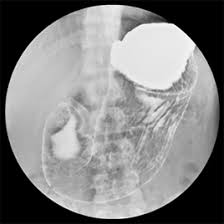

胃バリウム

潰瘍やポリープの可能性。

再検査は胃カメラでの精査がオススメです。

- 便潜血陽性・胃バリウム異常 → なるべく早く(1か月以内)